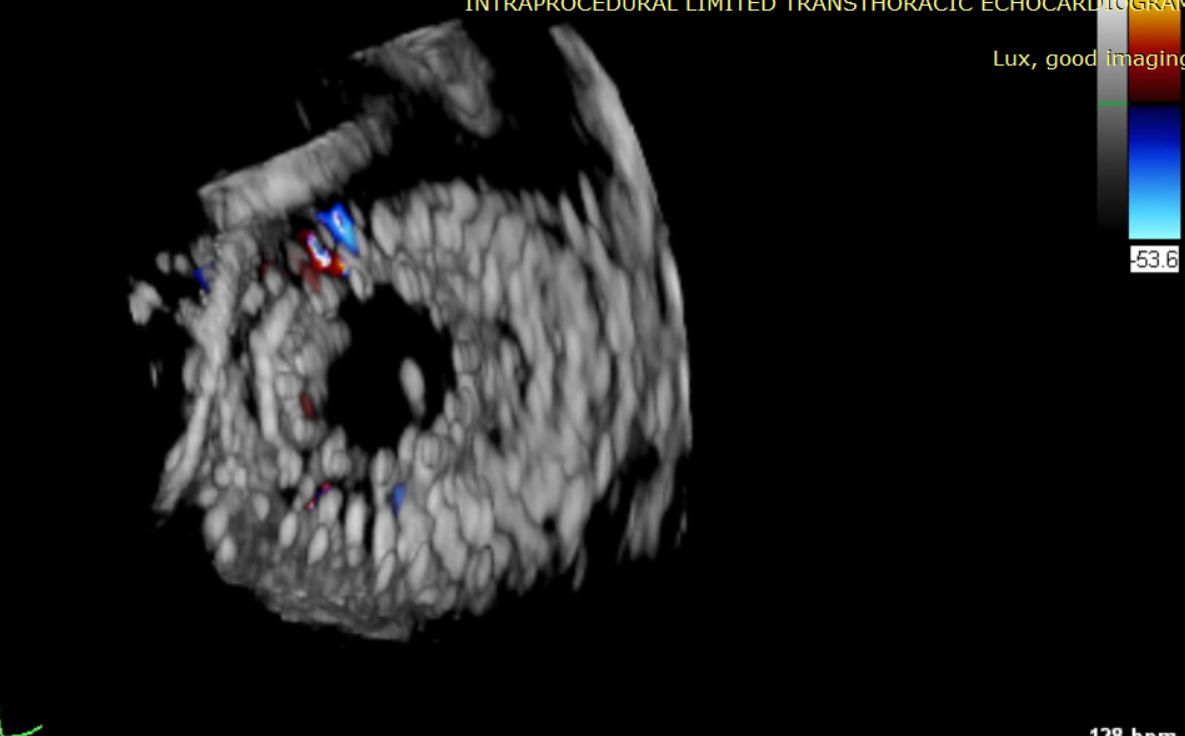

術(shù)前超聲提示大量三尖瓣反流

術(shù)中輸送器在超聲引導(dǎo)下調(diào)整位置

術(shù)后超聲提示僅殘余輕微瓣周漏